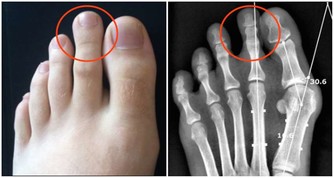

2、 四肢腫脹疼痛

四肢肢是人體供血的最末端,當血管堵塞後,四肢的供血和回血不足就會出現腫脹現象。四肢組織處於缺血缺氧狀態下就會伴隨有疼痛的表現,特別是靜脈血栓發生後,腫脹症狀更為明顯。